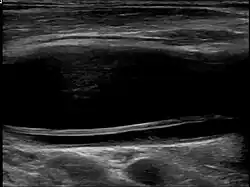

| Dissection in the carotid artery | |

| Diagnostic method | Ultrasound, MRI, MRA, CTA |

Carotid artery dissection can occur spontaneously or be triggered by trauma, including minor injuries, certain medical conditions, or activities that involve neck movement. It is a leading cause of stroke in young and middle-aged adults. The condition is typically diagnosed through imaging studies, such as ultrasound, magnetic resonance imaging (MRI), magnetic resonance angiography (MRA), or computed tomography angiography (CTA), which help visualize the blood vessels and detect abnormalities.